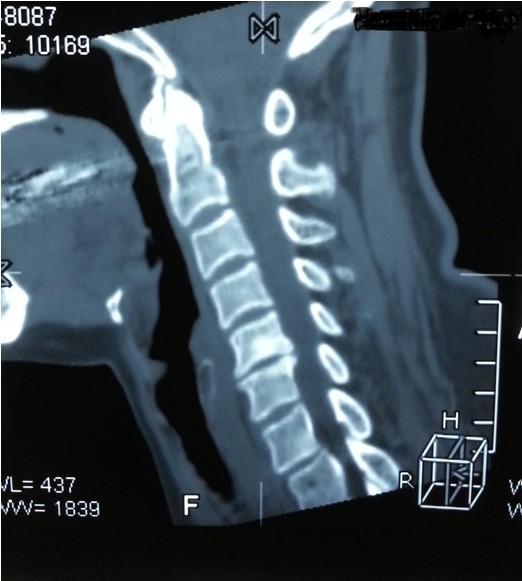

我院副院長兼脊柱科主任劉志安詢問病史后,詳細查體并攝片,發(fā)現(xiàn)患者是頸椎間盤突出,骨質(zhì)增生,壓迫頸椎神經(jīng),引起頸肩部酸脹難忍,雙手麻木乏力,若不盡快處理,癥狀將進一步加重,建議患者盡早手術(shù)治療,否則將喪失最后的手術(shù)時機,有致癱瘓的可能。

一開始,處于對手術(shù)以及住院費用的恐懼,患者要求保守治療,可是如此嚴重的椎間盤突出,保守治療根本無法解除對頸椎的神經(jīng)的壓迫。劉副院長詳細向患者講述其病情起因,發(fā)展,變化,轉(zhuǎn)歸,并表示,患者頸椎手術(shù)總費用預(yù)計在5萬以內(nèi),報銷后自費約4萬左右,考慮患者家庭困難,可聯(lián)系紅十字基金會予以適當(dāng)?shù)难a貼,考慮再三,最終患者選擇到我院手術(shù)治療。手術(shù)結(jié)束后,患者慢慢開始恢復(fù),頸肩部酸脹不適癥狀消失,雙手麻木乏力癥狀較術(shù)前大為緩解,兩周后出院,患者及家屬對手術(shù)治療效果,醫(yī)生護士服務(wù)態(tài)度,以及花了3萬元就解決困擾多年的疾病均表示非常滿意。